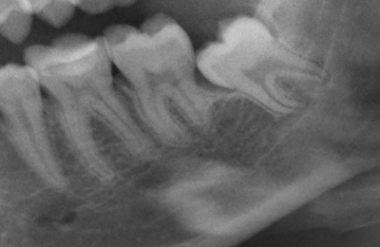

Bei einer Zahnextraktion wird der komplette Zahn entfernt. Eine operative Zahnentfernung kann bei brüchigen Zahnwurzeln notwendig werden oder wenn ein Zahnhals zerstört, stark beschädigt, die Zahnwurzel gekrümmt oder abgewinkelt ist oder wenn die gesamte Zahnsubstanz durch Karies stark geschädigt ist. Auch verlagerte, teilweise oder ganz unter dem Zahnfleisch liegende Zähne werden operativ entfernt.

Eine Zahnextraktion, d.h. das Entfernen eines Zahnes, ist ein Routineverfahren, das in den meisten Fällen unter örtlicher Betäubung erfolgen kann. Bei komplizierter Lage des Zahnes, bei Extraktion mehrerer Zähne oder auf Wunsch des Patienten kann der Eingriff auch unter Narkose erfolgen